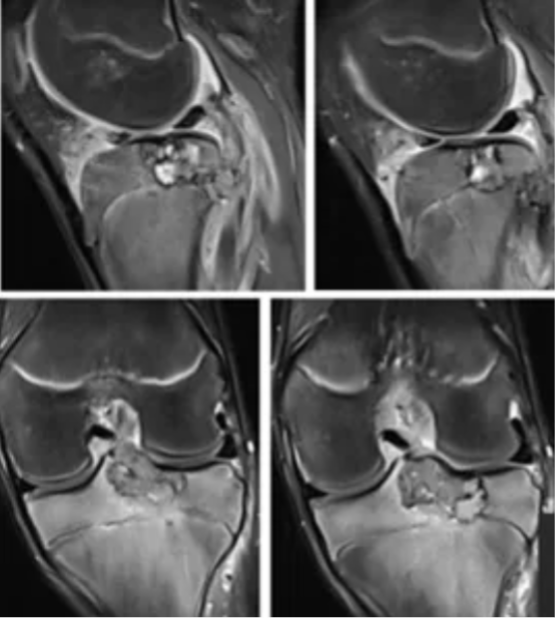

外院初诊影像:

读片:胫骨近端骨骺区密度不均匀透亮影,生长板以上地图样骨质破坏,直径约3cm,伴有薄层硬化边。磁共振上T1WI呈低或等信号,T2WI呈高低混杂不均匀信号,伴有骨髓水肿。